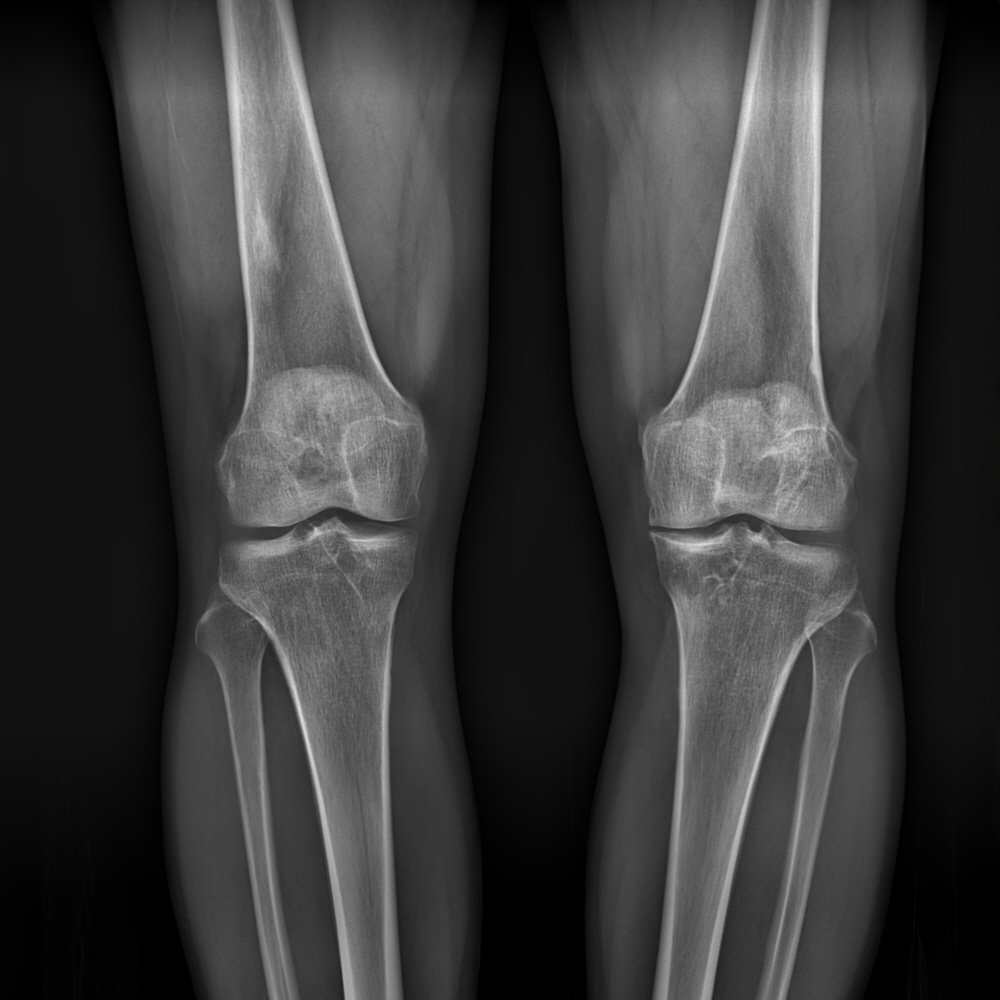

(KL Grade 1)

(KL Grade 2)

(KL Grade 3)

(KL Grade 4)

무릎 엑스레이 검사를 통해 관절염의 진행단계를 평가하는 방법으로 초기, 중기, 후기, 말기의 4단계로 나누어 진단하는 방법으로 방사선 사진 상 관절부위의 이상골격(관절간격 유지여부, 골극 형성, 연골하 경화소견 등)을 나타내는 평가지표이며, Grade III이상은 중등도 이상의 손상이 있음을 의미합니다.

KL Grade 1

임상적으로 의심스러운 퇴행성관절염 및 미미한 골 증식이 보임

KL Grade 2

경도 퇴행성관절염. 관절간격이 유지는 되나 골극이 형성되는 단계

KL Grade 3

중증도 퇴행성관절염, 골 증식이 grade2 에 비해 뚜렷하며 골극형성뿐 아니라 연골 마모에 의해 관절간격도 좁아지게 되는 단계

KL Grade 4

심각한 퇴행성관절염으로 연골이 거의 다 닳아 관절간격이 소실되어 뼈끼리 맞닿게 되고 연골하 경화 및 다량의 골극형성이 되는 마지막 단계